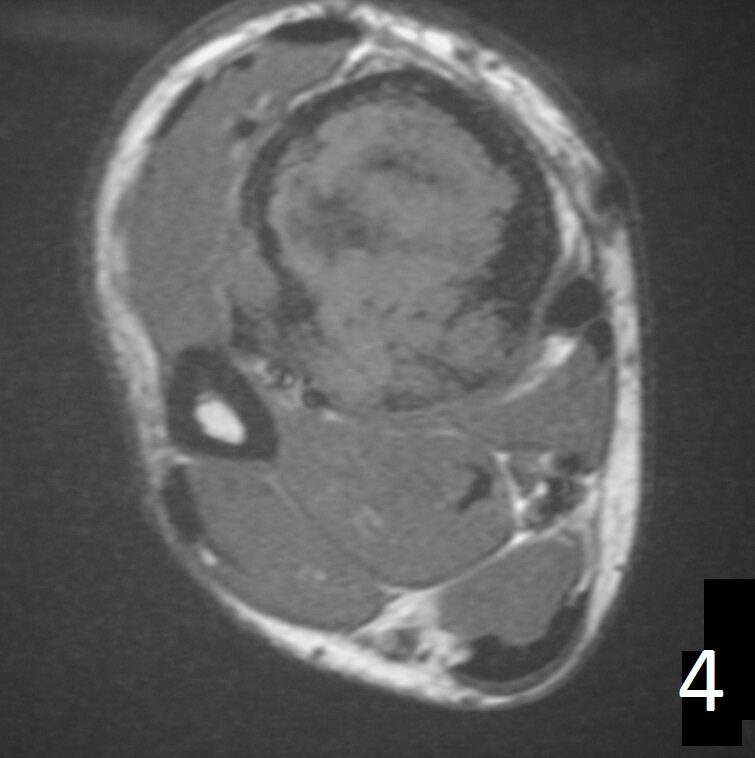

MRI (Fig. 4-5)

• Ideal to describe soft tissue involvement

• Sequences often follow that of fibrous tissue with low signal on T1 weighted and T 2 weighted images

Fig. 4-5: Axial MRI of leg demonstrates a tibia lesion with cortical destruction and soft tissue involvement.